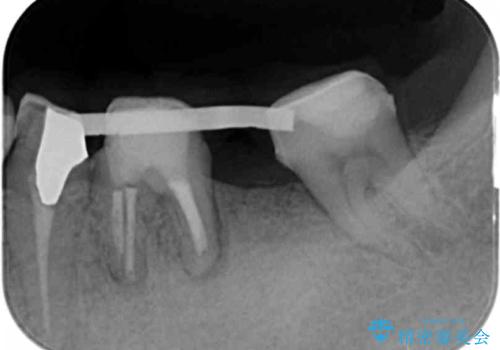

- 歯茎が腫れ、噛めない左下の治療を希望され来院されました。

精査をしたところ、歯の破により残すことが難しい状況で、親知らずと共に抜去を行いインプラントによる機能回復を計画します。